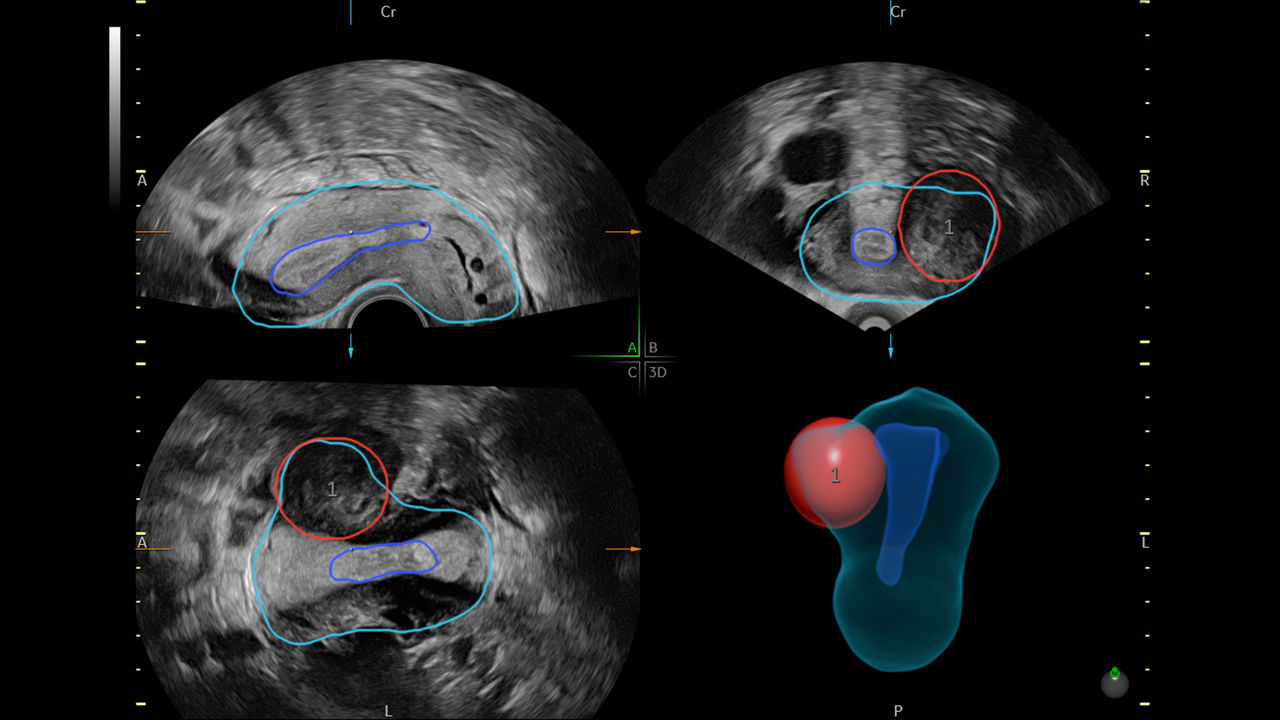

SonoGYN

Combines our Uterine Trace tool and Fibroid Mapping feature, an AI reporting tool that standardizes and streamlines fibroid documentation by mapping, measuring, and classifying fibroids in 3D.